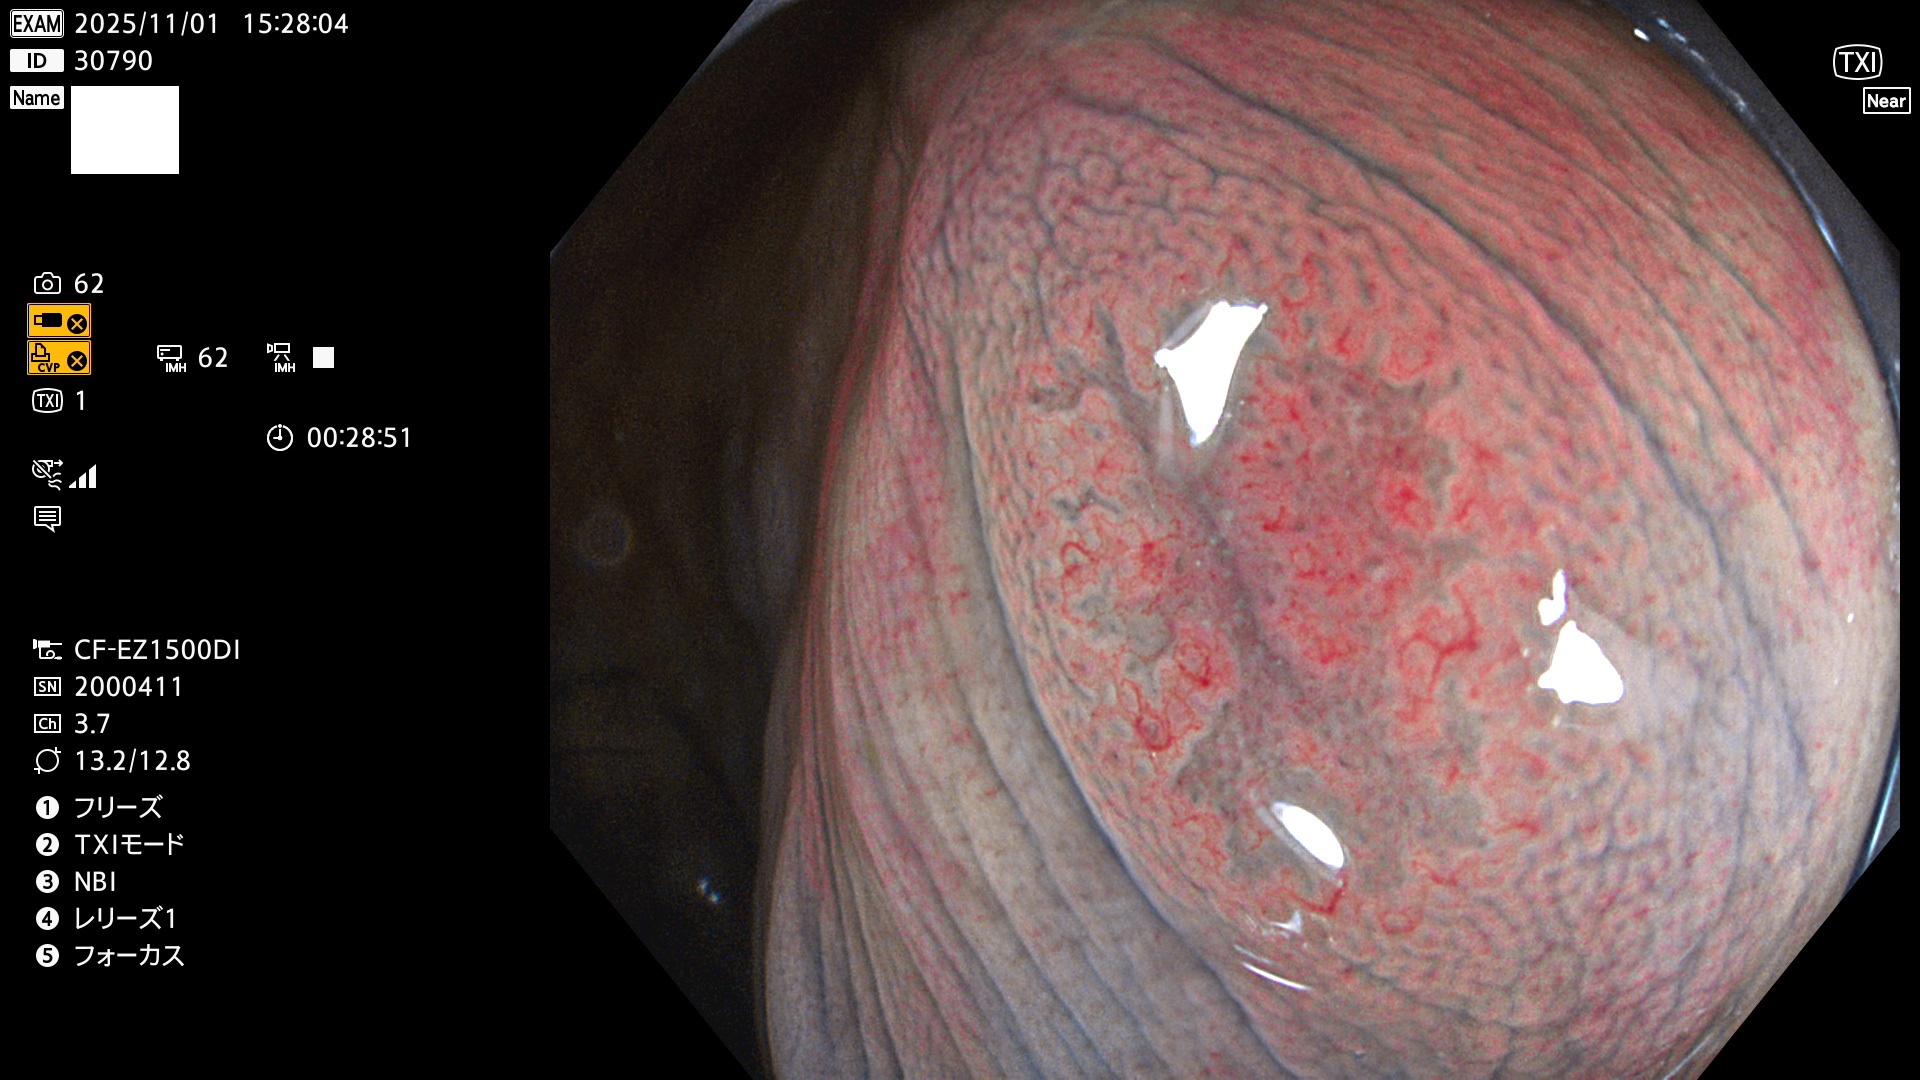

完全に平坦な物をUb、陥凹している物をUcと呼びます。Ubは認識が困難で、Ucはびらん(炎症)と紛らわしいために見落とされやすく、「内視鏡後・大腸癌」の原因になります。

専門的)Uc=De Novo癌? 内視鏡の解像度が低かった時代、このような説もありました。しかし今日の高精度内視鏡では良性の微小なUc型腺腫(APC遺伝子異常の腺腫)が日常的に見つかります。Ucこそが多段階発癌(Adenoma-Carcinoma Sequence)のMain Routeです。

専門的)細胞生物学的Ucの再定義UcをPitと形態学で定義するのは医学的には全く不毛です。Ucの本質はIntraTumor HeterogenityとTumor Dormancyが微小病変に見られる点です。これは早い腫瘍進化=ゲノム不安定性を意味します。そのような病変は隆起型でも形態によらずUcと定義すべきです。なぜなら1年後には陥凹し典型的Uc(最悪の場合NPG癌)になるからです。

毎週の検査(木・金・土・日)に発見されたUbとUc型・腺腫を、その週の日曜の夜にUPし1週間、提示します。

2025年10月30日〜11月2日の4日間(40件)9個 (Uc_ADR=9個/40人=23%)